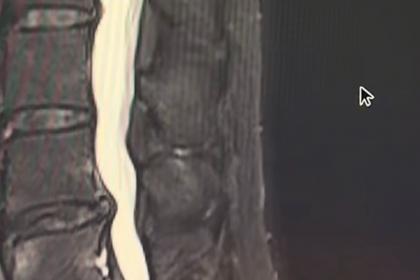

在家人建议下,我特意从辽宁来到北京解放军总医院(301医院),挂了神经外科姜红振副主任医师的号。姜主任耐心听我描述病情,仔细看了我带来的核磁共振片子,发现我是“腰椎硬膜外脂肪增多症”,硬膜囊受压呈现出典型的“Y”字型改变。

姜主任解释说,我这种情况是椎管内的脂肪组织异常增生,压迫了神经,导致了我的疼痛和麻木症状。他建议我接受一种微创手术——UBE技术(单侧双通道内镜手术),可以直接去除压迫神经的多余脂肪组织,同时不用动椎间盘,程度保护脊柱稳定性。